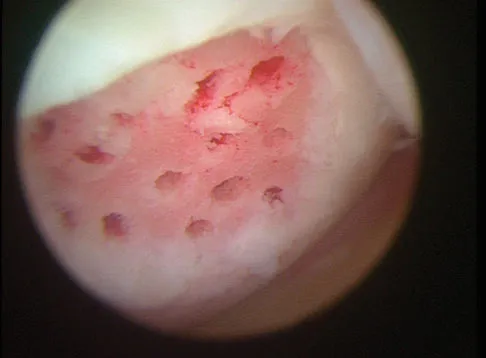

A 30-year-old patient reports chronic medial knee pain and swelling. Figure 9a shows an articular cartilage lesion observed during arthroscopy. The surgeon decides to treat the lesion with the microfracture technique seen in Figure 9b. A biopsy of the repaired tissue 1 year after treatment is likely to show which of the following findings?